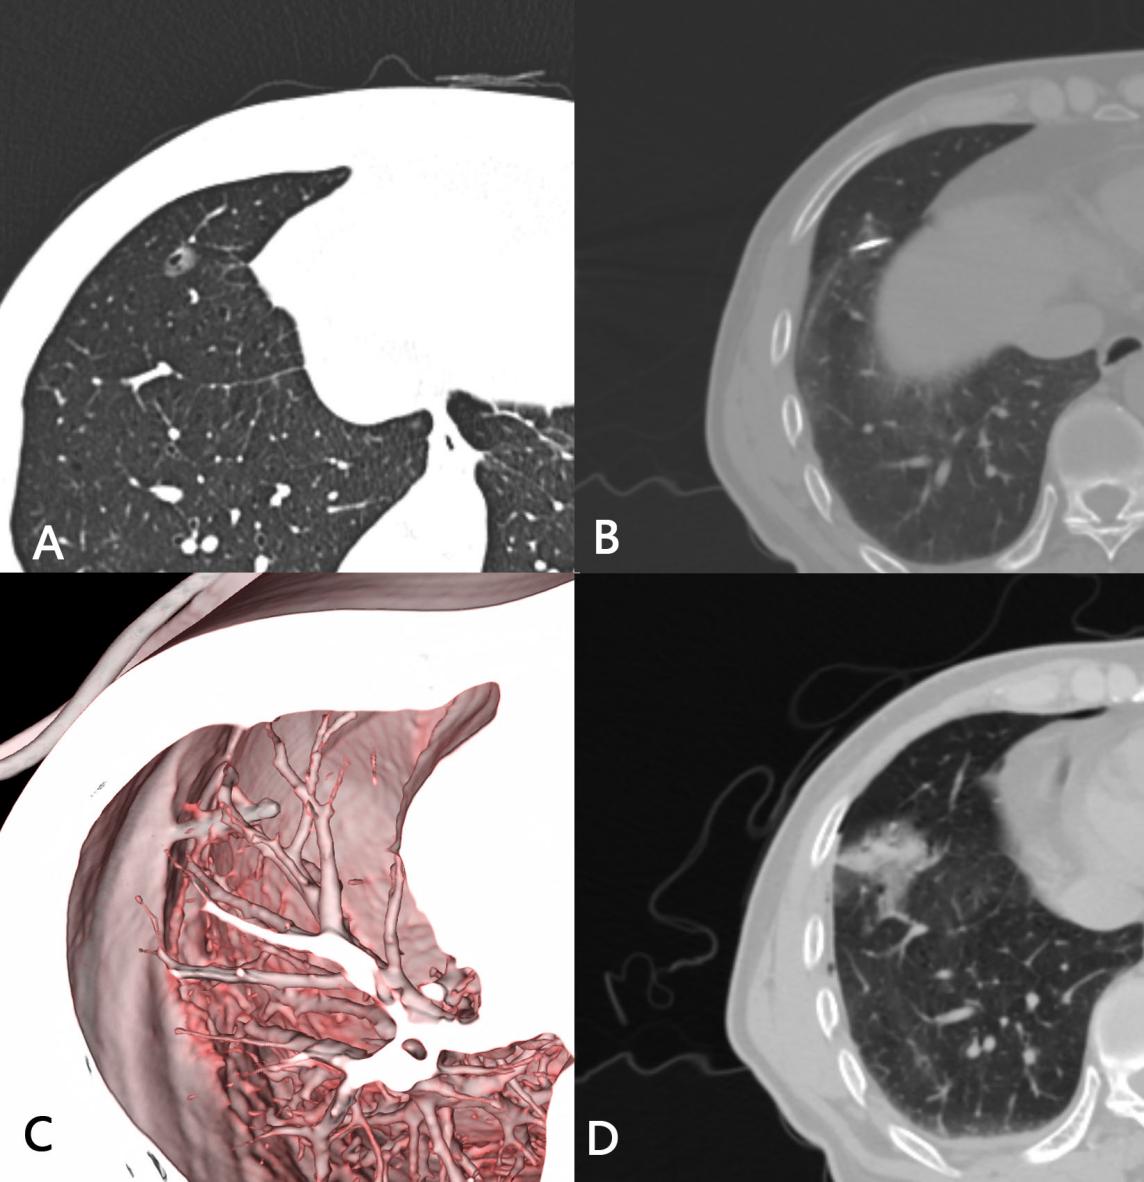

肺磨玻璃结节是胸部CT检查中常见的影像学表现,部分结节存在恶变风险,及时精准的治疗对保障患者健康至关重要。该患者肺腺癌术后2年筛查,显示右肺下叶磨玻璃结节影不断增大,考虑为高危结节,因肺功能无法耐受再次手术,到我院介入中心肺结节门诊进行咨询。为进一步控制病情,我院介入医学中心团队经过充分评估与讨论,决定对结节进行消融手术,因结节位于右肺下叶,易受呼吸运动影响,故决定采用穿刺手术导航机器人辅助进行CT引导下经皮肺结节射频消融术,以实现对病灶的精准清除,同时最大程度减少手术创伤。

与前者对比,穿刺手术导航机器人具有“CT影像与智能传感一体化”的显著技术优势。团队医生通过CT扫描获取的影像资料,在机器人系统上规划出最优穿刺路径。随后,借助穿刺机器人的导航定位与高精度操作能力,顺利将射频消融针准确穿刺至右肺下叶磨玻璃结节影处。为确保消融针位置完全适宜,团队医生再次进行CT扫描确认,随后分两次开展射频消融治疗。整个操作过程平稳流畅、精准无误,最大限度降低了对周围正常组织的损伤。同时,得益于机器人辅助,显著减少了CT扫描次数,不仅缩短了手术时间,更切实减轻了患者的身心压力与经济负担。治疗结束后,CT复查结果显示,消融区已完全覆盖原病灶,治疗效果达到预期。